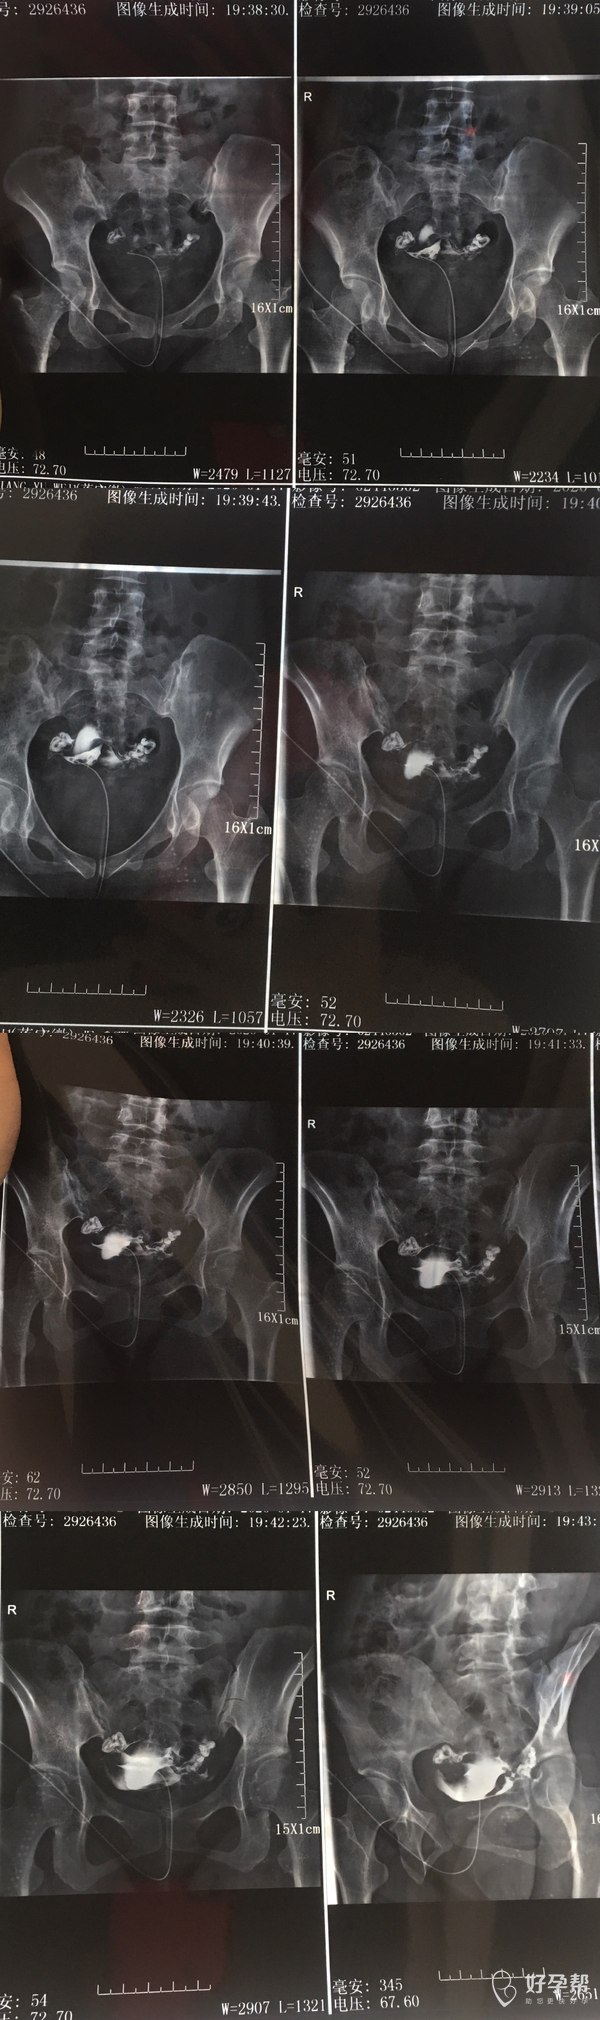

分析一下输卵管造影片给出下一步治疗方案

您好,输卵管堵塞是可以通过手术治疗的。输卵管手术的方法比较多:腹腔镜手术、注水腹腔镜手术、宫腔镜腹腔镜联合导丝介入手术等等,堵塞粘连的程度不同,采取的手术方法是不同的。试管婴儿也是可以选择的,只是试管一次性的费用较大,成功率只有20--30%。希望能慎重选择。试管婴儿是体外受精-胚胎移植技术的俗称,是指采用人工方法让卵细胞和精子在体外受精,并进行早期胚胎发育,然后移植到母体子宫内发育而诞生的婴儿。